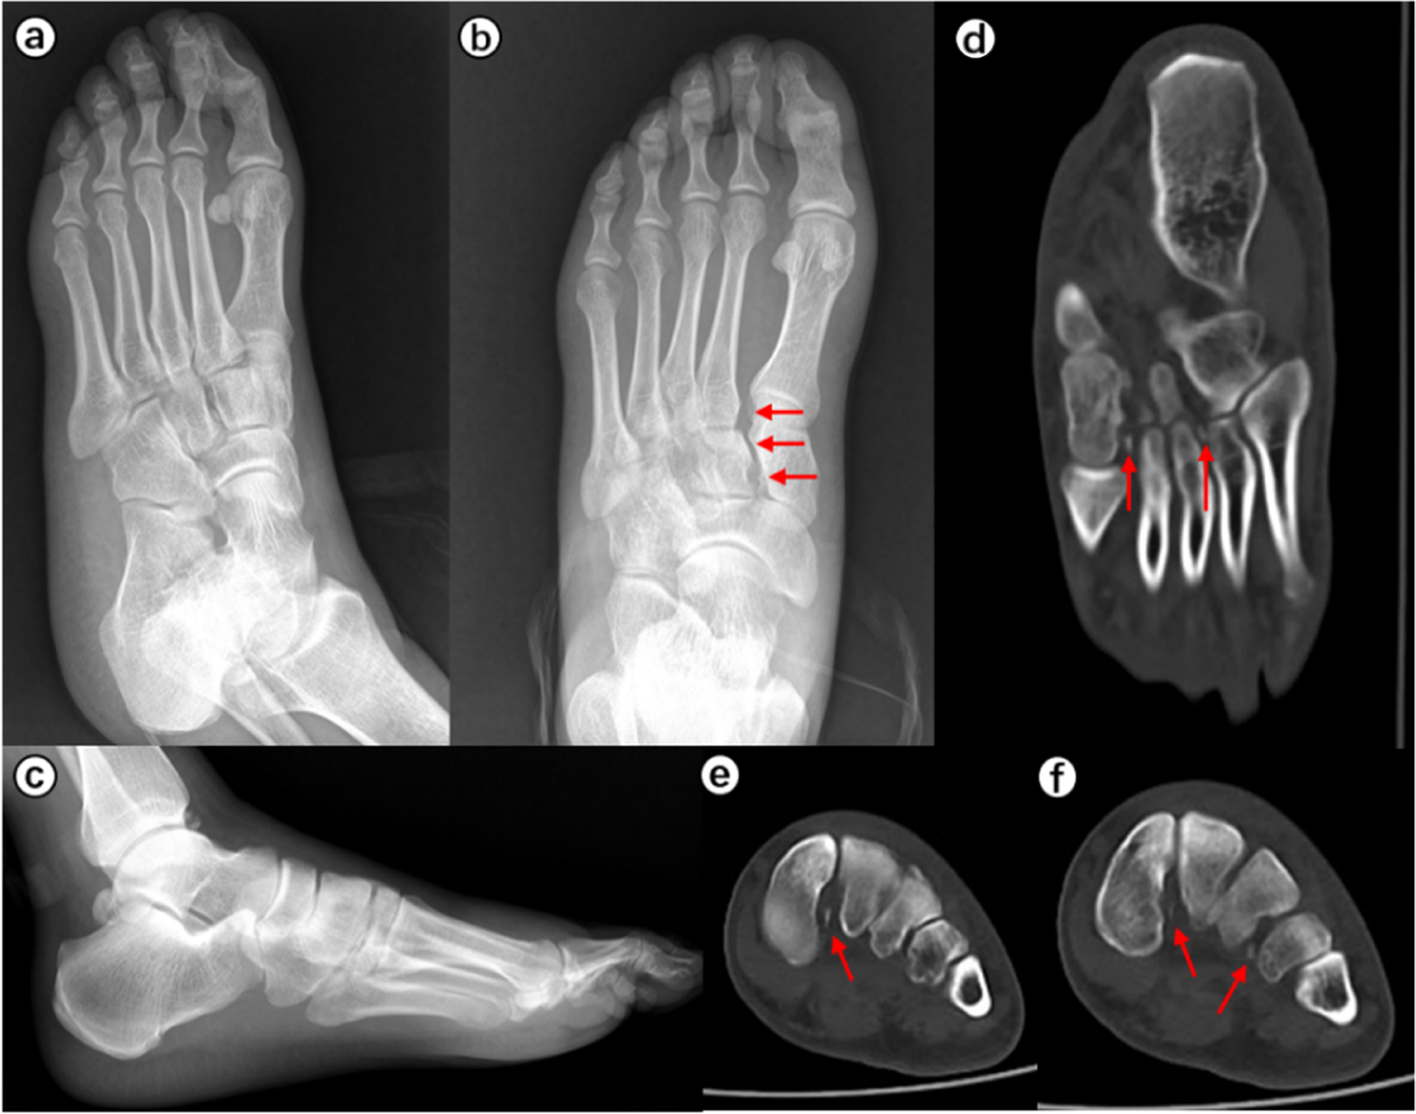

When the surgeons were asked to re-evaluate their initial treatment strategies after assessing the CT images (Table 5), the mean alteration rate was 21.9% (observer A, 28.3%; observer B, 15.6%). This represented a significant difference in alteration rates between the two observers (p < 0.001). Typical case images are shown in the figures (Figs. 1, 2, 3 and 4).

A 30-year-old female hurt her right foot after slipping. Chiodo-Myerson’s classification: three-column injury; Displacement classification: non-displaced injury. Observer A made the wrong diagnosis for two times, and changed the initial treatment option (conservative treatment to surgery) after evaluating CT image. Observer B made the correct diagnosis at the second time, and changed the initial treatment option (conservative treatment to surgery) after evaluating CT image. a-b The Lisfranc injury was easily missed on plain X-ray. c-e The plantar intra-articular fractures of the base of the first to fourth metatarsal bones are shown on computed tomography images. The red arrows indicate the fracture fragments